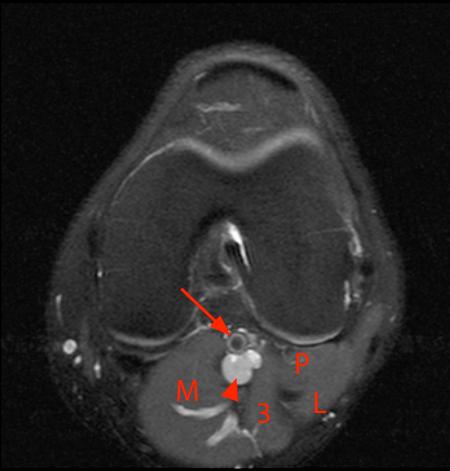

12 photos of the knee muscle anatomy mri. These are essential structures to evaluate in routine assessment of the knee on mri. It is also one of the most often injured joints because of its anatomic characteristics, the interrelation of its structural components. Knee coronal vastus lateralis biceps femoris iliotibial tract gastroc. Learn about knee anatomy muscle with free interactive flashcards. (lateral) popliteal a + v. Tips to keep joints healthy. Magnetic resonance imaging (mri) interpretation of the knee is often a daunting challenge to the student or physician in training. Radiology imaging medical anatomy human anatomy and physiology anatomy study. Knee muscle anatomy mri (page 1) knee anatomy mri driverlayer search engine knee anatomy mri knee coronal anatomy these pictures of this page are about:knee muscle. Master leg and knee anatomy using our topic page. (medial) acl peroneus longus 14 mri evaluation of meniscal damage size configuration of meniscus and signal pattern depth and width of altered signal location within meniscus 14. Mr arthrogram knee loose osteochondral lesion.

Mri knee anatomy cross patella sectional muscles sartorius femur surface epicondyle popliteus gastrocnemius muscle condyle atlas imaging body fascia. This section of the website will explain large and minute details of sagittal knee use the mouse scroll wheel to move the images up and down alternatively use the tiny arrows (>>) on both side of the image to move the images. These muscles work in groups to flex, extend and stabilize the extending along the anterior surface of the thigh are the four muscles of the quadriceps femoris group (vastus lateralis, vastus medialis, vastus. (medial) acl peroneus longus 14 mri evaluation of meniscal damage size configuration of meniscus and signal pattern depth and width of altered signal location within meniscus 14. Mr arthrogram knee loose osteochondral lesion. Want to learn more about it? Knee anatomy francesc malagelada jordi vega pau golanó the knee is the largest joint in the human body and one of the most complex from a functional point of view. Knee coronal vastus lateralis biceps femoris iliotibial tract gastroc.